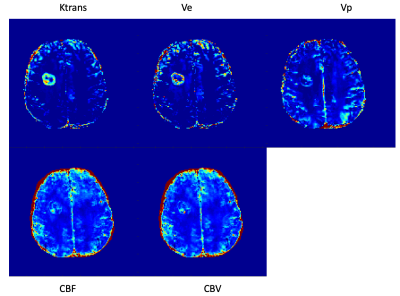

Figures 3 and 4 show examples of multiparametric MR images of a patient with brain metastases (lung cancer) and a patient with brain metastases (pulmonary sarcomatoid), respectively.

Figure 4. MT-DICE images of a patient with brain metastases due to pulmonary sarcomatoid. Heterogeneously increased Ktrans, Vp, Ve, CBV, and CBF are shown.